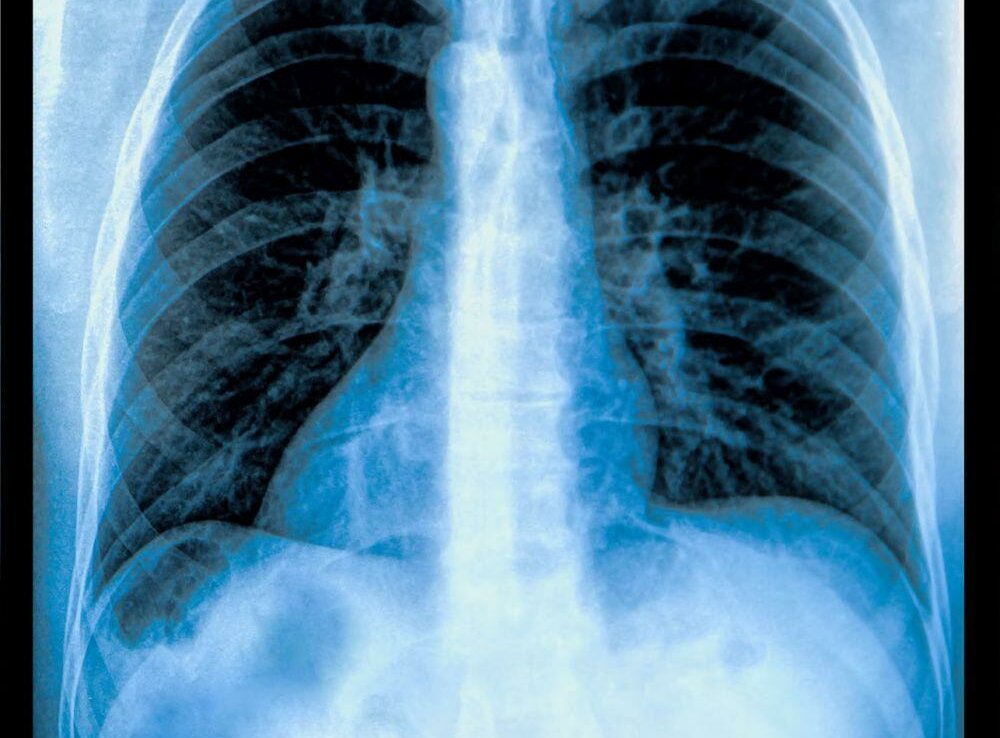

Verschiedene Stadien Der erste Kontakt mit dem Bakterium führt nach etwa sechs bis acht Wochen zu einem positiven Tuberkulinhauttest. Stellt man beim Röntgen der Lunge einen kleinen Entzündungsherd mit einer örtlich begrenzten Lymphknotenreaktion fest, liegt eine Primärtuberkulose vor, selten befindet sich dieser Primärkomplex außerhalb der Lunge.